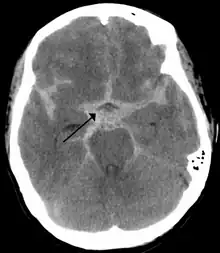

As first postulated by Harvey Cushing, raised intracranial pressure is the primary cause of the Cushing reflex.[3] Furthermore, continued moderate increases in cranial pressure allows for the Cushing reflex to occur. In contrast, rapid and dramatic pressure rises do not allow for the mechanism of the reflex to sufficiently take place.[12] Elevated intracranial pressure can result from numerous pathways of brain impairment, including: subarachnoid hemorrhages, ischemia, meningitis, trauma, including concussions, hypoxia, tumors, and stroke. In one study, it was confirmed that raised ICP due to subarachnoid hemorrhaging causes mechanical distortion of the brainstem, specifically the medulla. Due to the mechanism of the Cushing reflex, brainstem distortion is then swiftly followed by sympathetic nervous system over activity.[13] In addition, during typical neurosurgical procedures on patients, especially those involving neuroendoscopic techniques, frequent washing of the ventricles have been known to cause high intracranial pressure.[7] The Cushing reflex can also result from low CPP, specifically below 15 mmHg.[14] CPP normally falls between 70-90 mmHg in an adult human, and 60-90 mmHg in children.